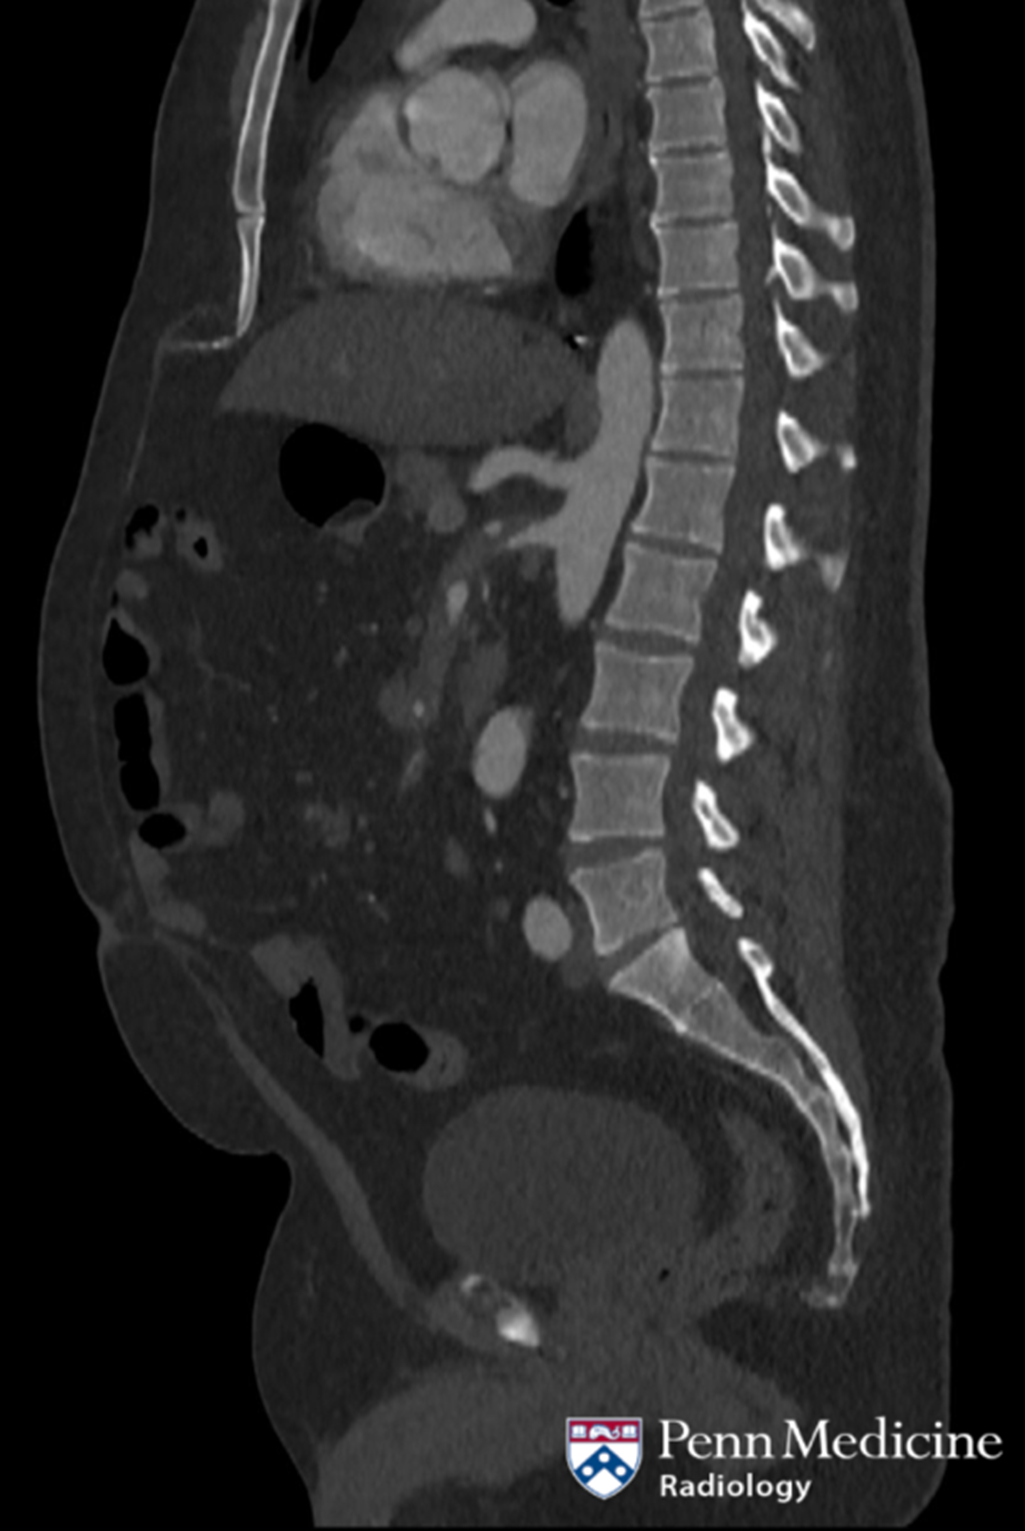

Cases of the Week

Check out our Cases of the Week!